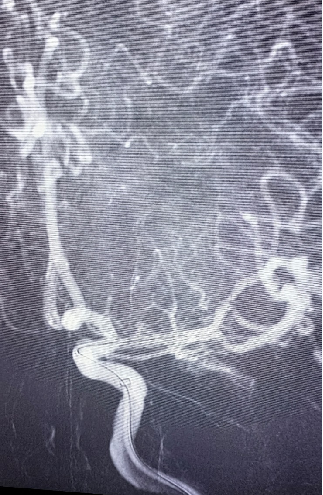

治疗中影像

在微导丝辅助下将赛诺神畅颅内药物洗脱支架NOVA DES®2.25*10mm于大脑中动脉狭窄处行支架成形术。

导丝怎么扩【载药时代 球扩天下】NOVA DES®颅内药物洗脱支架在大脑中动脉重度狭窄中的应用两例!_https://www.jmylbn.com_新闻资讯_第18张

导丝怎么扩【载药时代 球扩天下】NOVA DES®颅内药物洗脱支架在大脑中动脉重度狭窄中的应用两例!_https://www.jmylbn.com_新闻资讯_第19张

球扩后狭窄解除。